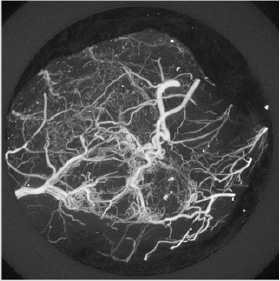

We used Sutent in this study as an anti-angiogenic compound to quantify the vascular normalization in response to two regimens. Sutent (SU11248, sunitinib malate, Pfizer, Inc., New York, NY, USA) is a small-molecule, multi-target tyrosine kinase inhibitor with high affinity for the PDGF and VEGF receptors [18]. Dual delivery of VEGF and PDGF-BB returned more mature vessel formation than either single growth factor. Sutent has demonstrated anti-tumor activity and inhibition of angiogenesis in clinical trials [19,20]. It was approved by the FDA in January of 2006 to treat renal cell carcinoma and imatigib-resistant Gastrointestinal Stromal Tumors (GIST). Imaging technology has advanced significantly over the last decade for drug research and clinical diagnoses. Various imaging modalities with proper imaging analysis methods have been utilized to reveal the function and anatomy of vascular structures in differing spatial and temporal resolutions [21,22]. Contrastenhanced CT is able to reconstruct three-dimensional (3-D) vascular structures with resolution of a few microns. In this study, the isotropic voxel dimension of all images in the vehicle and the treated groups was 16 m (Figure 1A & 1B).

Figure 1A: Maximum Intensity Projection (MIP) of 3-D tumor-induced vasculature. A two-week 3-D tumor vasculature MIP image illustrates the excessive abnormal sprouting and tortuosity in the entire tumor. The 3-D vascular structure was acquired by CT imaging modality with contrast agent injection. The isotropic voxel size of 3-D vasculature is 16 m.